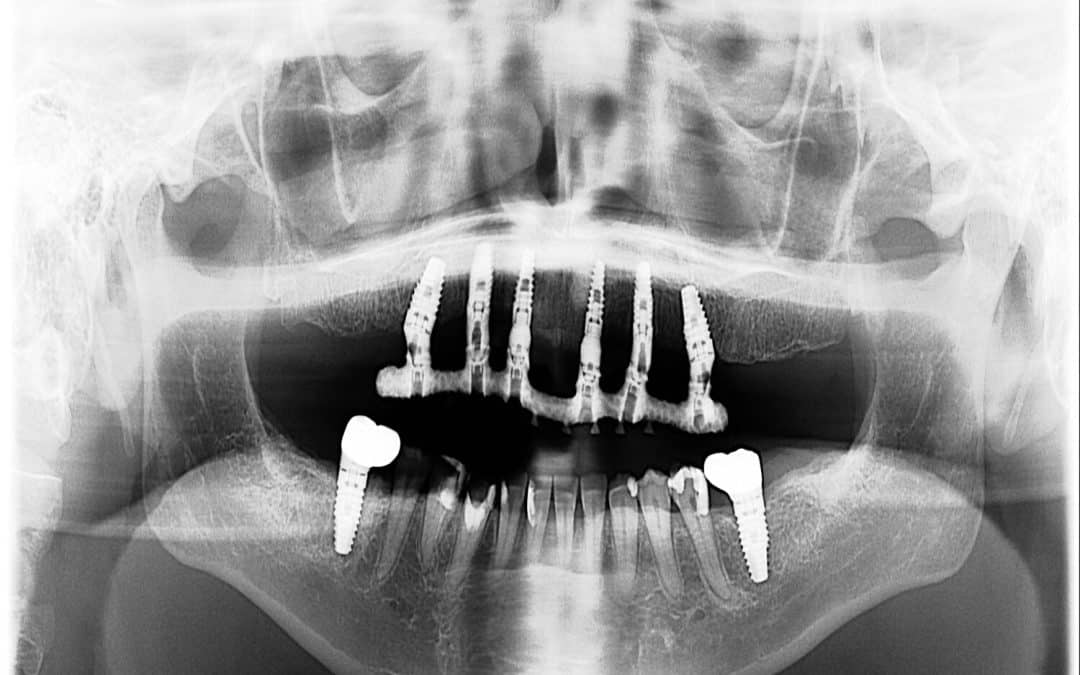

CC's dental implants with prosthesis removed at iHeart Dental

We started with detailed photos, digital scans, panoramic X-rays, and CBCT imaging to understand exactly what we were working with. From there, we designed a PMMA trial smile that allowed us to test how everything felt before moving to a final zirconia restoration.

Thankfully, the implants remained stable and fully integrated. Once the prosthesis was removed, it became clear that her natural gummy smile had not been properly accounted for in the original treatment. There simply was not enough space created for a well-balanced restoration.

Close-up images of the prosthesis removed show why a redesign was necessary.